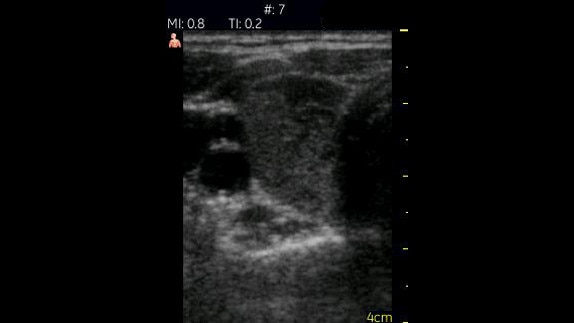

Hepatorenal Alan